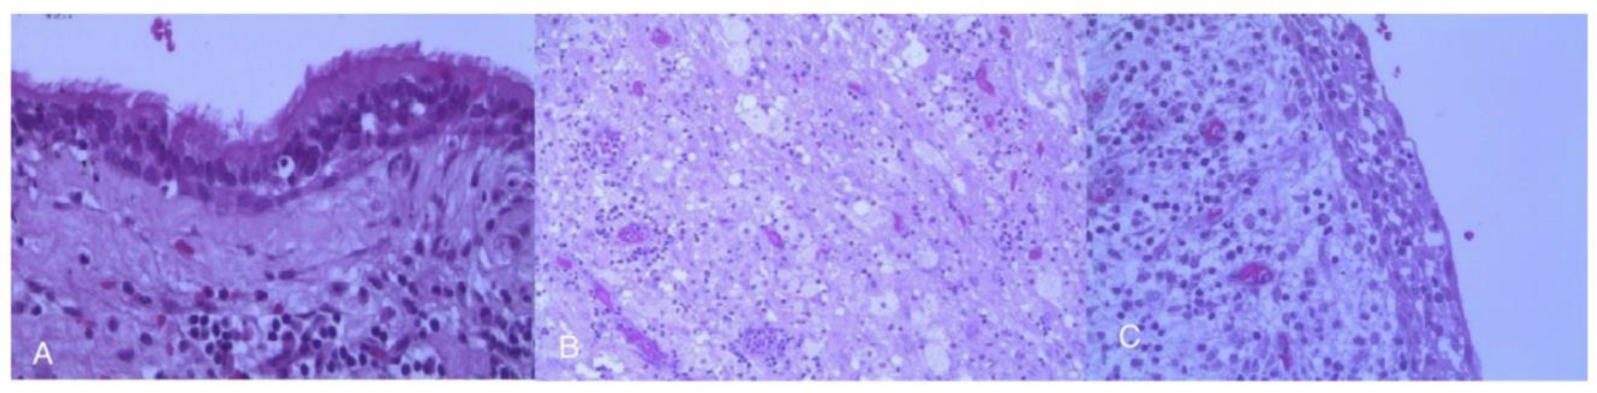

3.5. Spindle Cell Oncocytoma (SCO)

| 8. | Spindle Cell Oncocytoma | IP of 50%, Ds of 12 Gy, Dm of 24 Gy | 2013–2019 |